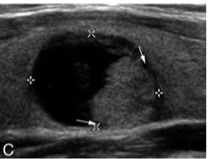

- Solid area within cyst suggests malignancy. 25% papillary ca. undergo necrosis- appear partially cystic